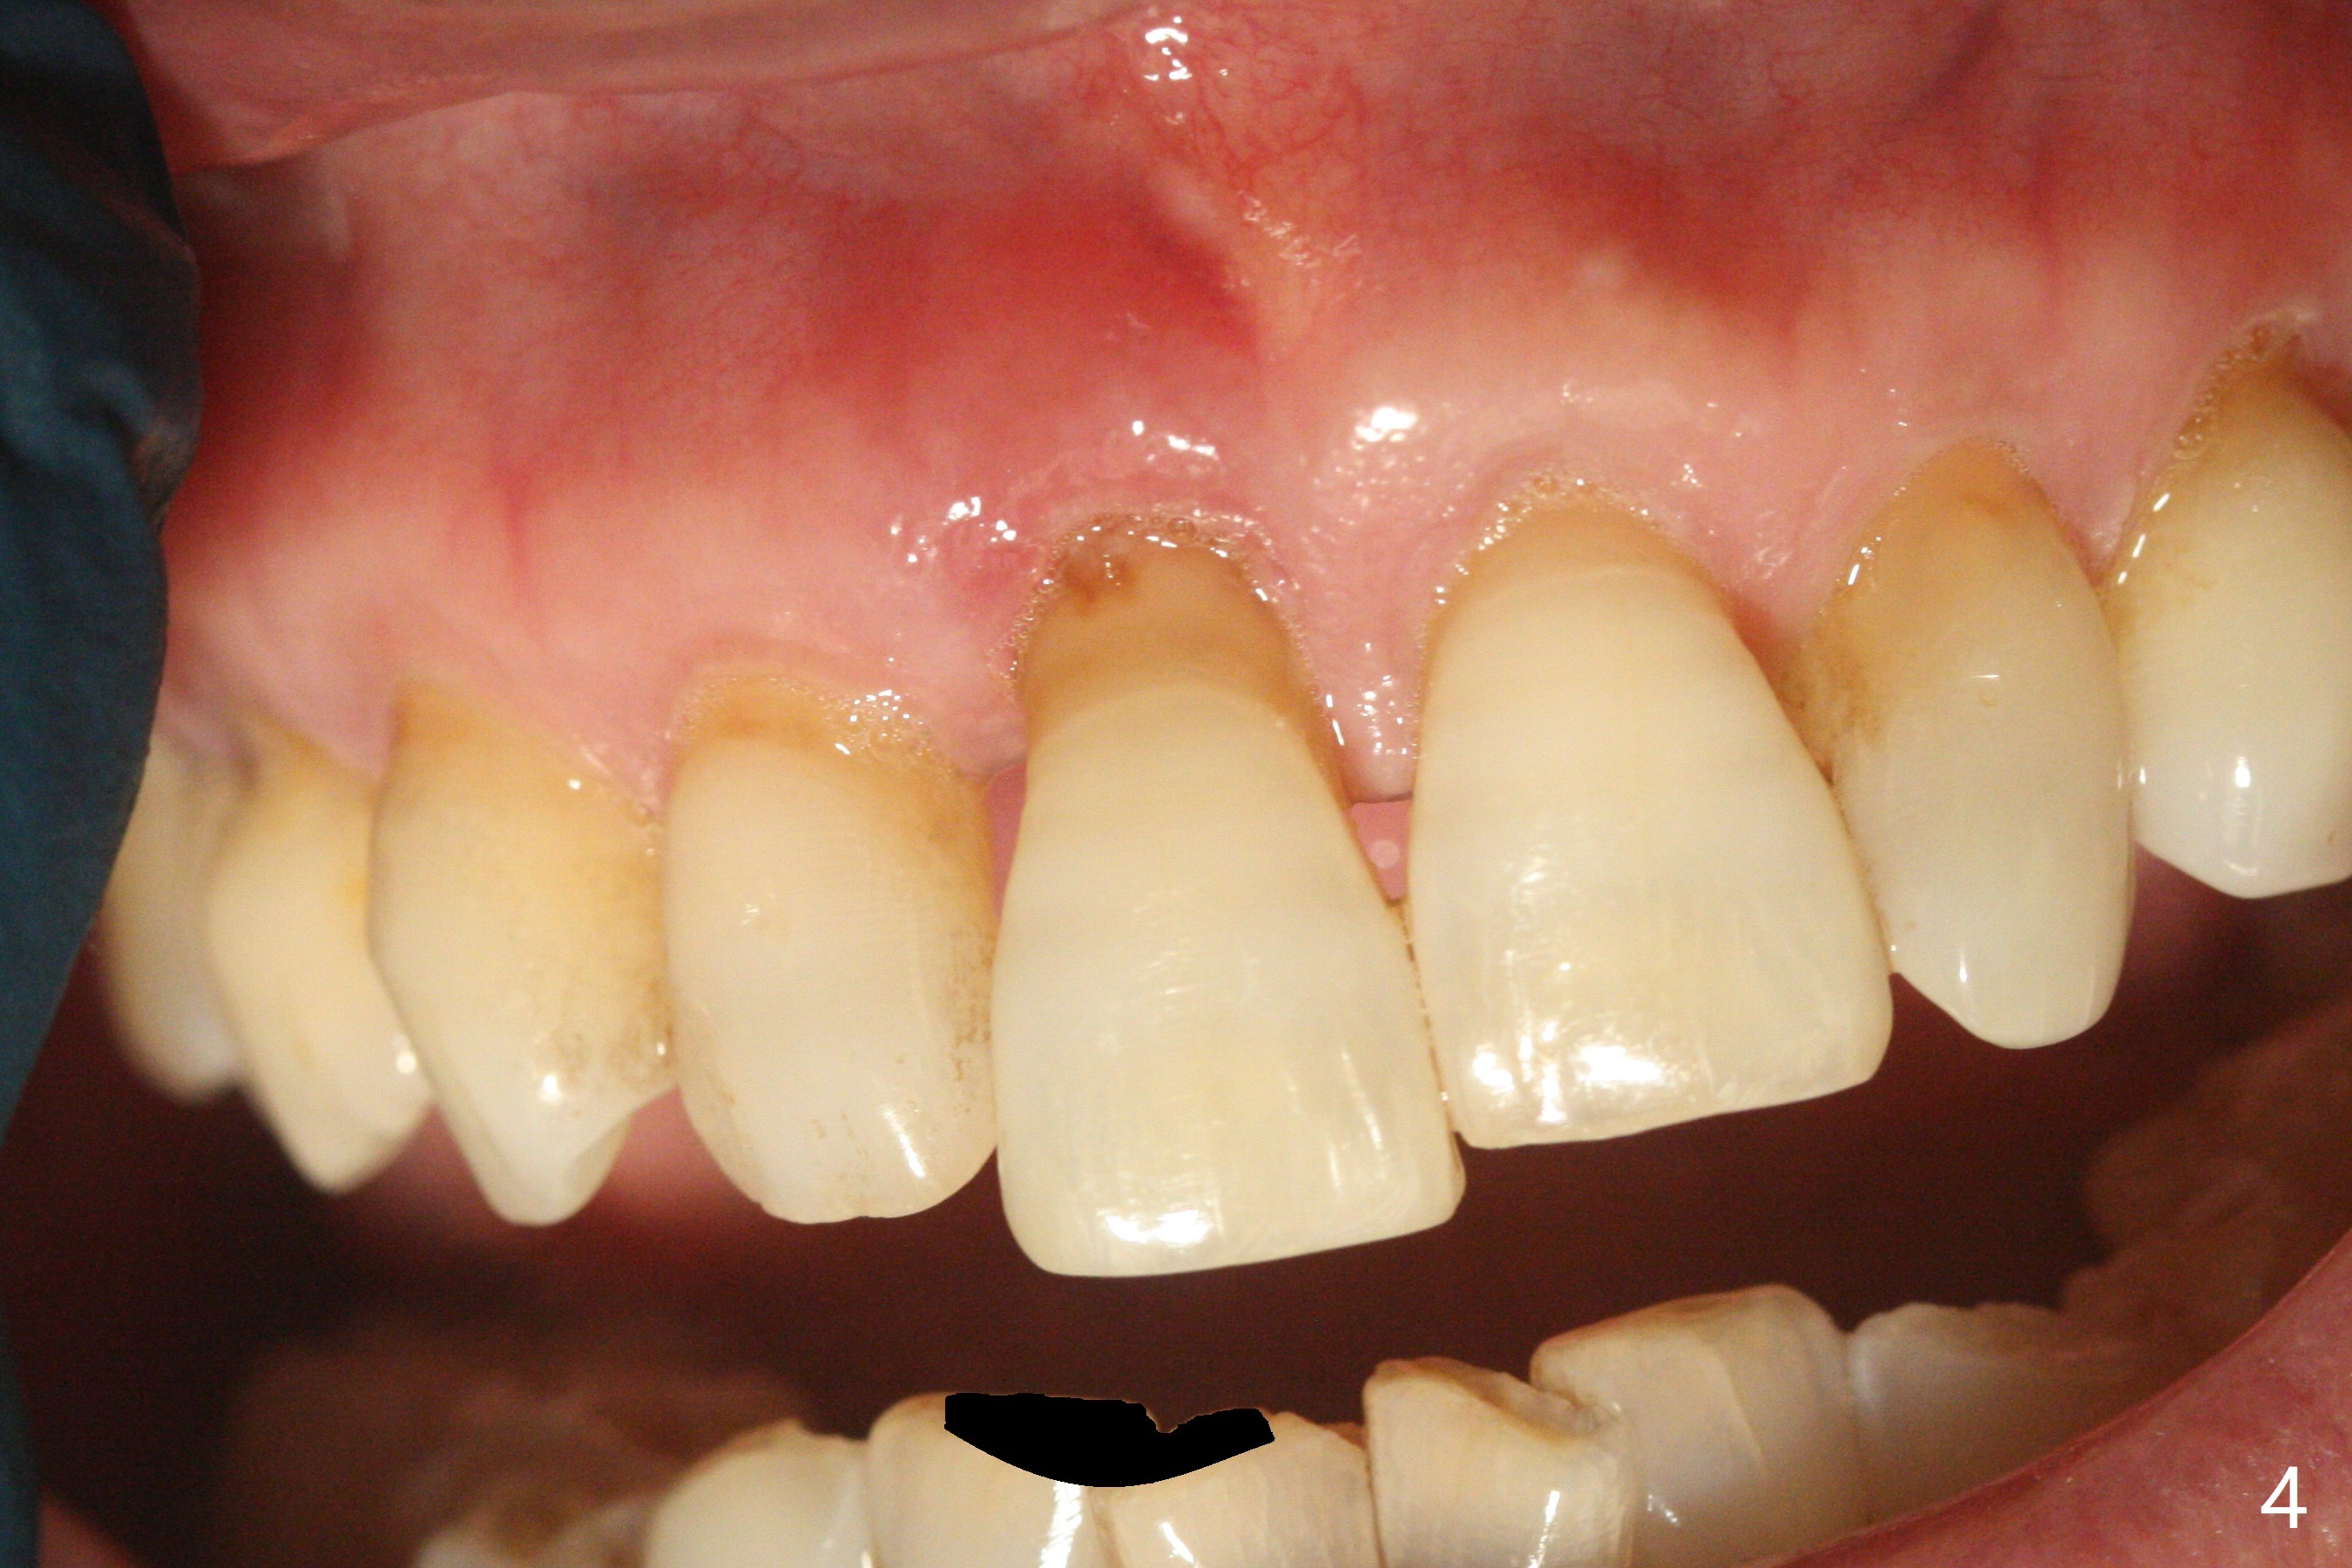

59岁女今天就诊,“上门牙快掉下来”,检查表明右上1延长(图一:长箭头),牙龈退缩(短箭头),红肿(*),颊侧骨板触诊不觉得塌陷(图二)。咬合时,患牙前移(图三),伸长的下切牙(图三,九:1,2)造成咬合创伤。因此拔牙前,将降低下门牙切缘(图四,五(黑色)),为临时牙冠创造足够修复空间。CT冠状切面显示颊侧(图六:B)骨板缺失,可以植入两段式植体(3.5x11.5 毫米),但是最细基台(4毫米直径,图七(粉红色和蓝色))显得太粗,不利于腭侧修复空间形成,而2.5x14(4)毫米一段式植体不仅创造更多颊侧植骨空间(图八(红箭头)),而且由于固有基台直径小(白箭头),容易形成腭侧修复空间。一旦前牙植体永久性修复完成,督促病人做三个第二磨牙植牙修复(图九:7),减少对前牙植牙创伤。临时牙冠不仅解决美观问题,而且固定骨粉,保持颊侧骨板隆起,维持牙龈缘和乳头。在大多数情况下,使用现成树脂牙冠(crown form)制作临时修复物,这个病例牙齿完整,截除的牙冠可以用来做临时牙冠。